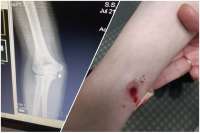

image 83Кб, 960x1280

Бизнесмен расстрелял семью на глазах ребёнка — за отказ бывшей вернуться к нему.

Всё произошло на шашлыках в Горнозаводском районе Пермского края. Мама, папа и их 11-летняя дочь решили отдохнуть на берегу речки Койвы. К ним присоединилась сестра женщины — 40-летняя завуч школы в посёлке Бисер Вероника Шинкевич.

Через несколько минут на пикник приехал и её экс-супруг — 57-летний предприниматель Сергей Шинкевич, который держит несколько продуктовых магазинов. Он заявил, что есть разговор к бывшей. Мужчина начал извиняться перед ней и умолял вернуться к нему. Та отказала. Сначала отвергнутый уехал, но около полуночи вернулся — уже с ружьём.

Шинкевич открыл огонь по родственникам. 11-летняя школьница успела позвонить в полицию и сообщить, что дядя стреляет по её родителям. Но помочь им уже не успели — все трое взрослых скончались на месте. У ребёнка сквозное ранение плеча. Девочка передана сотрудникам опеки. У убитой Вероники Шинкевич также остался несовершеннолетний сын.

Возбуждено уголовное дело статье 105 УК РФ («Убийство двух и более лиц»), сообщила «Ленте.ру» представитель управления Следственного комитета России по Пермскому краю Ирина Незнамова. По ее словам, подозреваемый задержан в своем доме в рабочем поселке Бисер утром следующего дня после массового убийства, 28 июня.